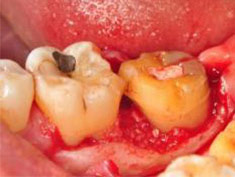

D圖為牙齦翻瓣清創後之頰側觀,#37其近心側有一寬且深,深達9毫米,型態為三壁之骨內缺損(three walls intrabony defect),頰側之根叉並無侵犯。

E圖為牙齦翻瓣清創後之舌側觀,其近心側繞舌側有一寬且深,深達5毫米,型態為合併雙壁、三壁之骨內缺損(combined two-three walls intrabony defect),舌側之根叉侵犯為1毫米。